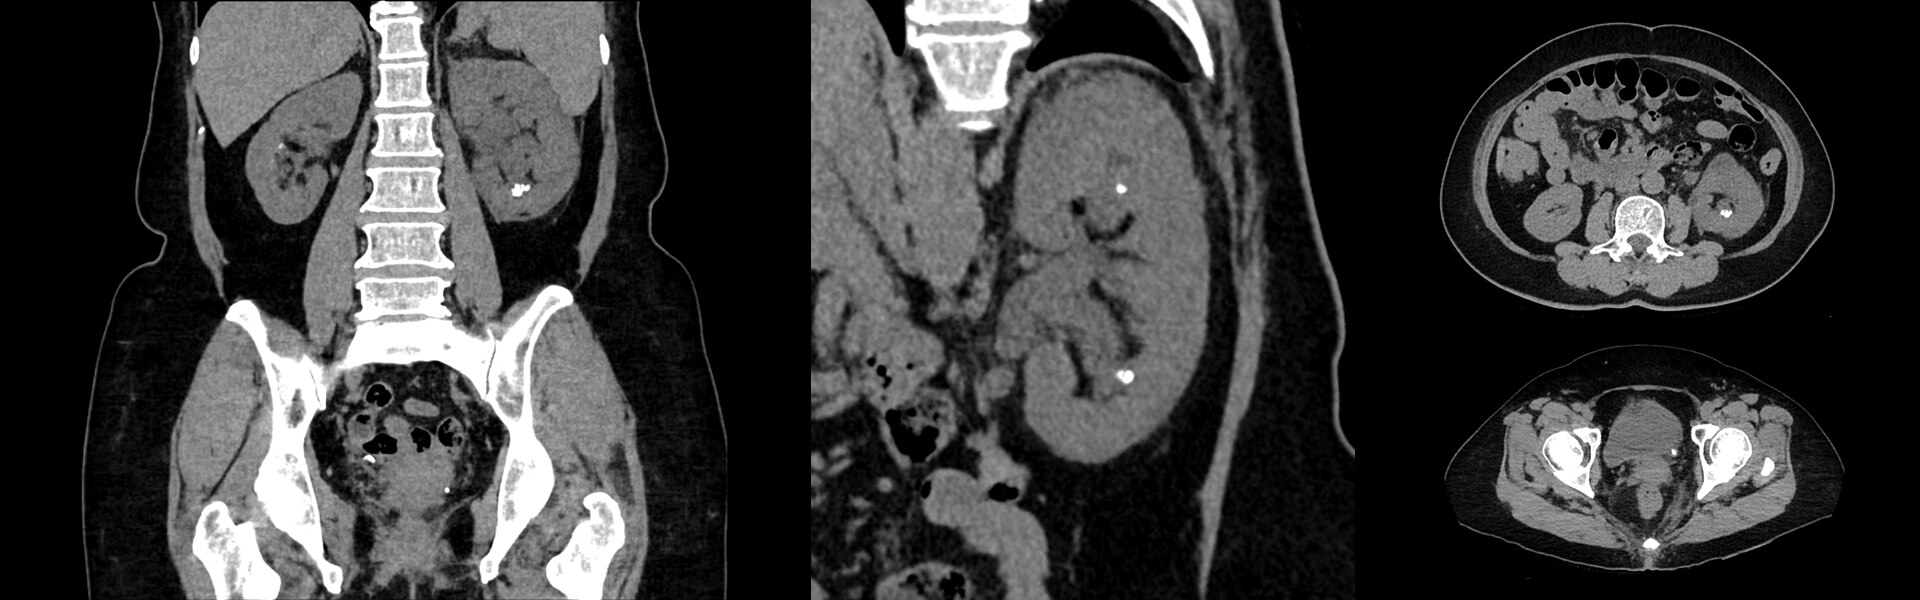

Images cliniques

Lésions multiples au niveau des jambes et du cou

Petite lésion de l'oreille et tumeur de la hanche.

Lésion cervicale à droite mesurant 6 mm.

Acnée visible sur le dos

Poumon droit, aine droite et tumeur derrière le genou droit.

Cancer de la tête et du cou.

Évolution du cancer après la radiothérapie. Minuscule cancer du sein.

Ganglions lymphatiques avec fixation de FDG au niveau de l’aisselle gauche (vaccination contre la COVID-19).